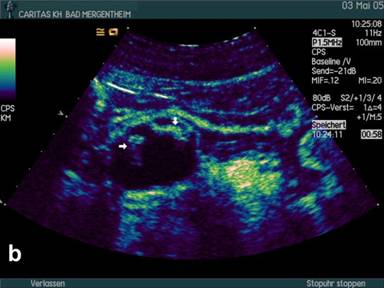

Mucinous Cystadenoma

During the study period we examined 11 patients by CEUS with mucinous neoplasia (all except one lesion located in the corpus or tail of the pancreas; 2 benign, 9 malignant; all operated). The mean diameter of the lesions was 61±18 mm (range: 40-83 mm). Using conventional B-mode mostly peripherally located solid nodules were displayed in 9 out of 11 patients (81.8%). Contrast enhancement was found in all 9 nodules (Figure 3). Isolated macrovessels transversing the cyst(s) could not be visualised.

Figure 3. B-mode imaging (a.) and contrast enhanced ultrasound (CEUS) (b.) in a patient with mucinous cystadenoma displaying the mainly cystic but partially also solid tumour. |